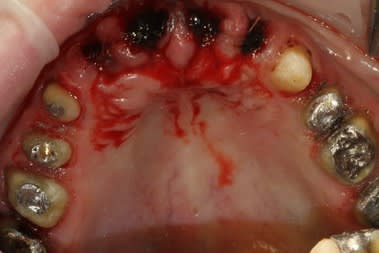

extract récente implant + Vitalos

essai de photos

votre avis?

moi, ce qui m'interpelle, c'est le choix de l'EEI qui t'oblige à te laisser embarquer dans une alvéole qui ne te donnera pas forcement le meilleur axe ni le meilleur centrage

pourquoi ce choix?